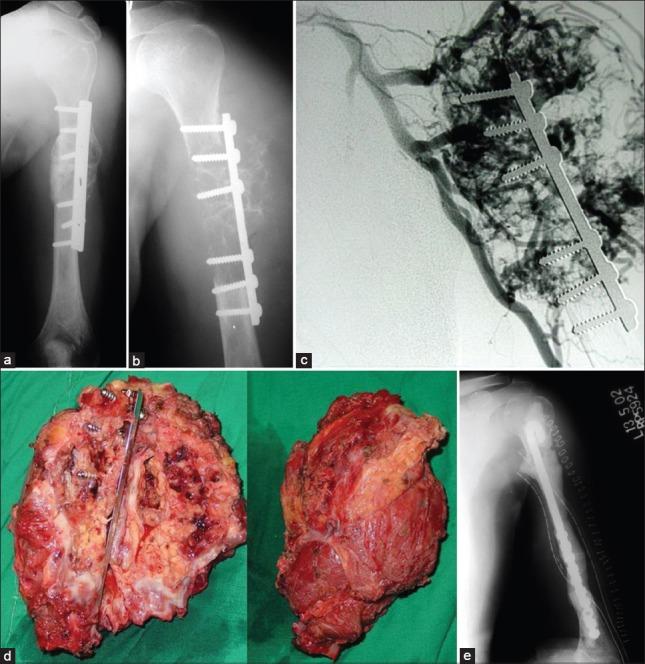

Skeletal metastasis is a common cause of severe morbidity, reduction in quality of life (QOL) and often early mortality. Its prevalence is rising due to a higher rate of diagnosis, better systemic treatment, longer lives with the disease and higher disease burden rate. As people with cancer live longer and with rising sensitivity of body imaging and surveillance, the incidence of pathological fracture, metastatic epidural cord compression is rising and constitutes a challenge for the orthopedic surgeon to maintain their QOL. Metastatic disease is no longer a death sentence condemning patients to "terminal care." In the era of multidisciplinary care and effective systemic targeted and nontargeted therapy, patient expectations of QOL, even during palliative end of care period is high. We lay emphasis on proving the diagnosis of metastasis by biopsy and histopathology and discuss imaging modalities to help estimate fracture risk and map disease extent. This article discusses at length the evidence and decision-making process of various modalities to treat skeletal metastasis. The modalities range from radiation including image-guided, stereotactic and whole body radiation, systemic targeted or hormonal therapy, spinal decompression with or without stabilization, extended curettage with stabilization, resection in select cases with megaprosthetic or biological reconstruction, percutaneous procedures using radio frequency ablation, cementoplasties and discusses the role of emerging modalities like high frequency ultrasound-guided ablation, cryotherapy and whole body radionuclide therapy. The focus lies on the role of multidisciplinary care, which considers complex decisions on patient centric prognosis, comorbidities, cost, feasibility and expectations in order to maximize outcomes on QOL issues.

骨转移是导致严重发病、生活质量(QOL)下降以及常出现早期死亡的常见原因。由于诊断率提高、全身治疗效果更好、患者带病生存时间延长以及疾病负担率上升,其患病率正在上升。随着癌症患者生存期延长以及身体成像和监测的敏感性提高,病理性骨折、转移性硬膜外脊髓压迫的发生率正在上升,这对骨科医生维持患者的生活质量构成了挑战。转移性疾病不再是宣判患者“临终关怀”的死刑判决。在多学科护理以及有效的全身靶向和非靶向治疗时代,即使在姑息性临终关怀阶段,患者对生活质量的期望也很高。我们强调通过活检和组织病理学来证实转移瘤的诊断,并讨论有助于评估骨折风险和描绘疾病范围的成像方式。本文详细讨论了治疗骨转移的各种方式的证据和决策过程。这些方式包括放疗,如影像引导放疗、立体定向放疗和全身放疗、全身靶向或激素治疗、有或无内固定的脊柱减压、扩大刮除术加内固定、在某些病例中进行假体或生物重建的切除术、使用射频消融、骨水泥成形术的经皮手术,并讨论了高频超声引导消融、冷冻疗法和全身放射性核素治疗等新兴方式的作用。重点在于多学科护理的作用,它考虑以患者为中心的预后、合并症、成本、可行性和期望等复杂决策,以最大限度地提高生活质量相关问题的治疗效果。